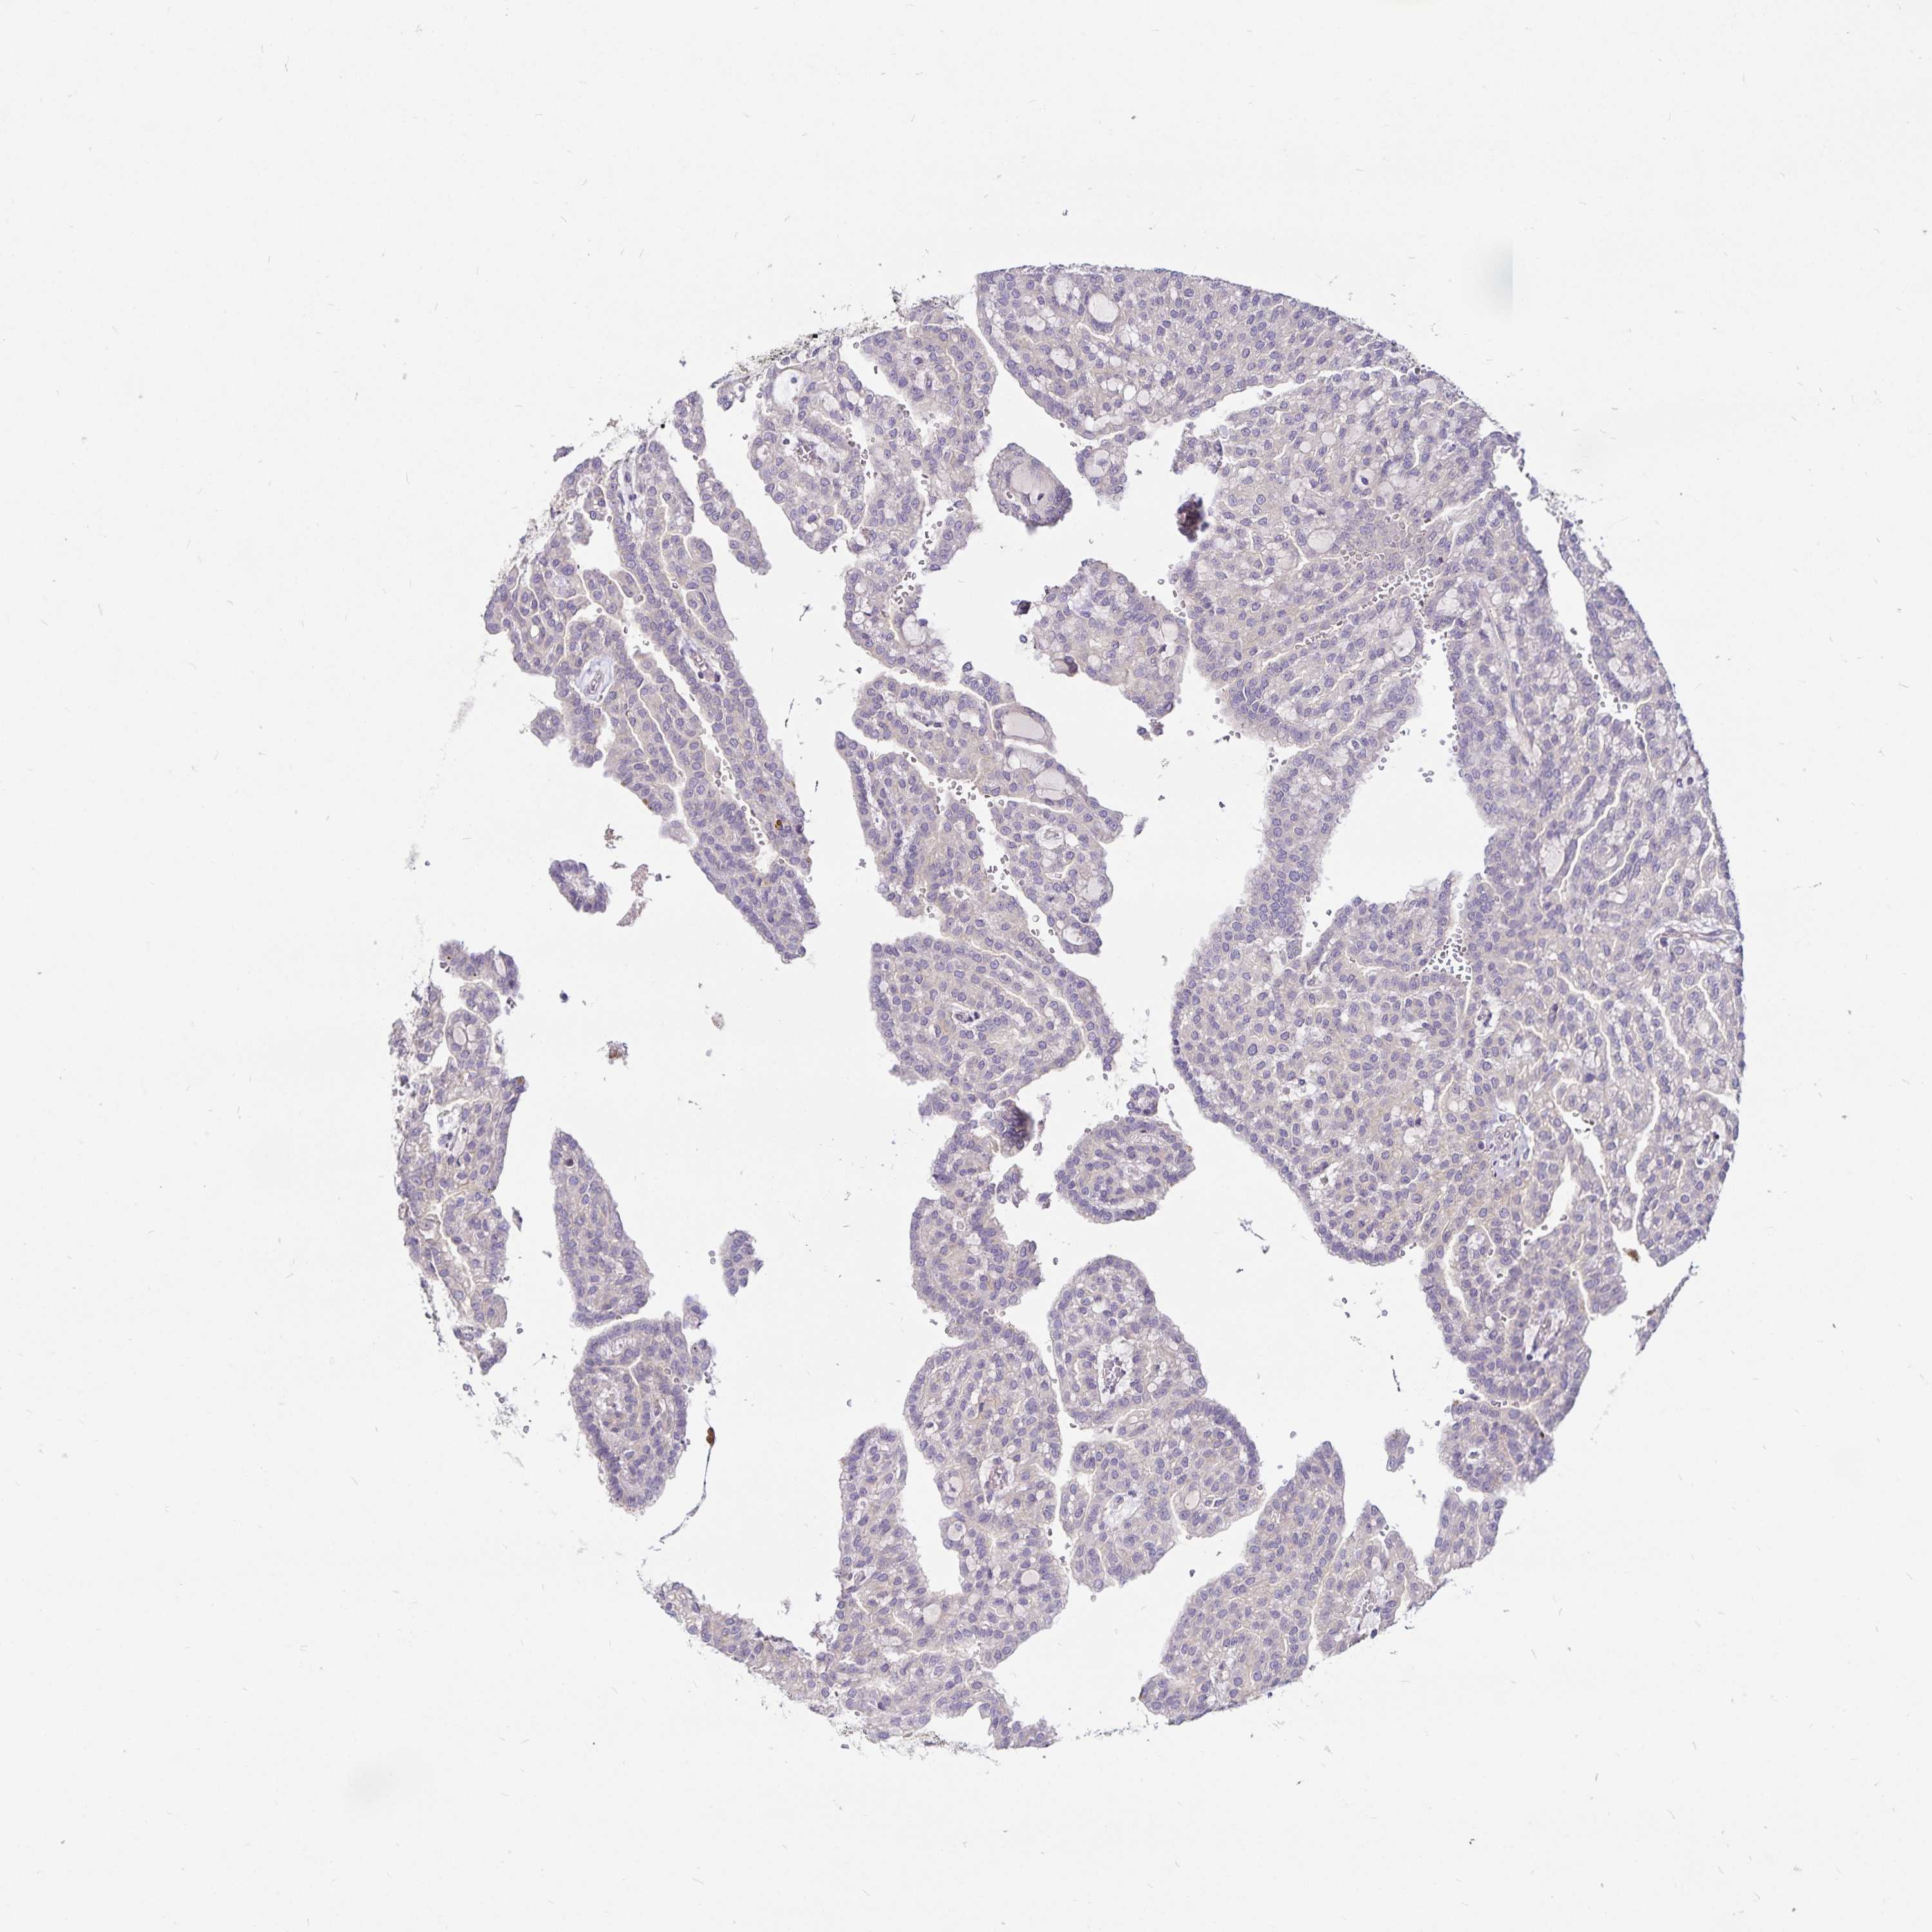

KIDNEY RENAL CLEAR CELL CARCINOMA (VALIDATION) - Interactive survival scatter ploti

The Survival Scatter plot shows the clinical status (i.e. dead or alive) for all individuals in the patient cohort, based on the same data that underlies the corresponding Kaplan-Meier plots. Patients that are alive at last time for follow-up are shown in blue and patients who have died during the study are shown in red.

The x-axis shows the expression levels (FPKM) of the investigated gene in the tumor tissue at the time of diagnosis. The y-axis shows the follow-up time after diagnosis (years). Both axes are complimented with kernel density curves demonstrating the data density over the axes. The top density plot shows the expression levels (FPKM) distribution among dead (red) and alive patients (blue). The right density plot shows the data density of the survived years of dead patients with high and low expression levels respectively, stratified using the cutoff indicated by the vertical dashed line through the Survival Scatter plot. This cutoff is automatically defined based on the FPKM cutoff that minimizes the p-score. The cutoff can be changed by dragging the vertical line or by entering a cutoff value in the square labeled "Current cut-off".

Under the Survival Scatter plot the p-score landscape (black curve; left axis) is shown together with dead median separation (red curve; right axis). Dead median separation is the difference in median mRNA expression between patients who have died with high and low expression, respectively. It is calculated as follows: median FPKM expression of dead patients with high expression - median FPKM expression of dead patients with low expression. This is intended to aid the user in visually exploring custom cutoffs and the associated p-scores and dead median separation.

Individual patient data is displayed and can be filtered by clicking on one or more of the category buttons on the top of the page. Categories describing expression level and patient information include: high, low, alive, dead, female, male and tumor stages. The scale of the x-axis can be toggled between linear and log-scale by clicking on the "x log" button. Mouse-over function shows TCGA ID, patient information and mRNA expression (FPKM) for each patient.

& Survival analysisi

Kaplan-Meier plots summarize results from analysis of correlation between mRNA expression level and patient survival. Patients were divided based on level of expression into one of the two groups "low" (under cut off) or "high" (over cut off). X-axis shows time for survival (years) and y-axis shows the probability of survival, where 1.0 corresponds to 100 percent.

GNG12 is not prognostic in Kidney Renal Clear Cell Carcinoma (validation)

Best expression cut offi

Based on the FPKM value of each gene, patients were classified into two groups and association between prognosis (survival) and gene expression (FPKM) was examined. The best expression cut-off refers the FPKM value that yields maximal difference with regard to survival between the two groups at the lowest log-rank P-value. Best expression cut-off was selected based on survival analysis .

When clicking on this number, the vertical dashed line indicating cut-off, the interactive survival plot, and the Kaplan-Meier curve will be adjusted to show results based on the best expression cut-off.

: 52.9

P scorei

Log-rank P value for Kaplan-Meier plot showing results from analysis of correlation between mRNA expression level and patient survival.

N/A

TCGA RNA samplesi

RNA-seq data is reported as average FPKM (number Fragments Per Kilobase of exon per Million reads), generated by the The Cancer Genome Atlas (TCGA) .

Normal distribution across the dataset is visualized with box plots, shown as median and 25th and 75th percentiles. Points are displayed as outliers if they are above or below 1.5 times the interquartile range. FPKM values of the individual samples are presented next to the box plot.

Average pTPM 72.5

Number of samples 100